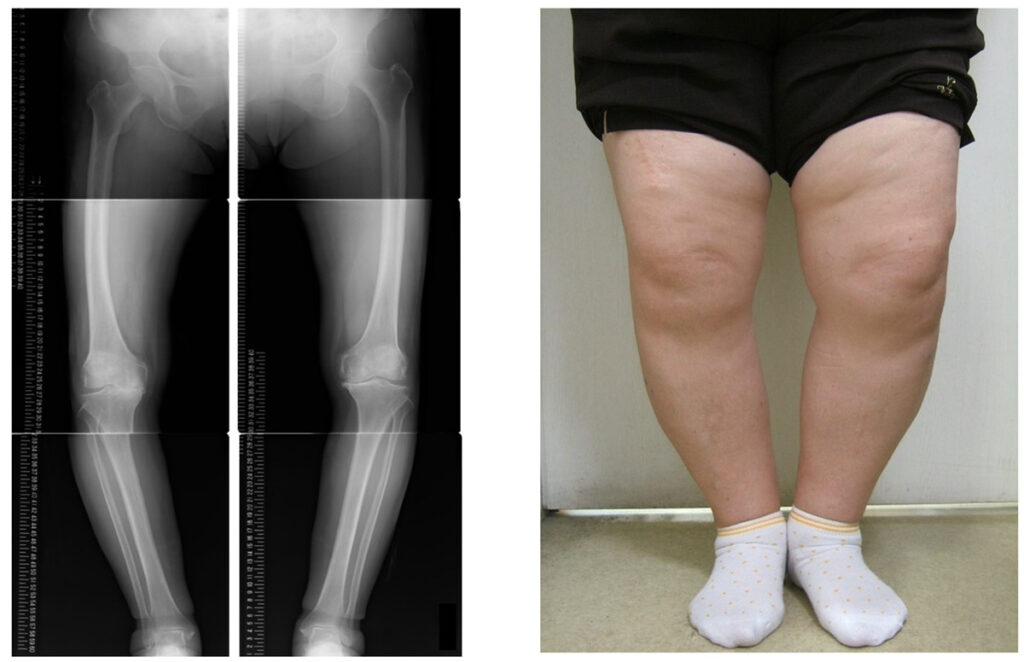

3〜4年前から膝が痛く、整形外科に行ってレントゲンも撮ったのですが異常なしと言われ、どうしていいのか悩んでいたのですが、もしかしたら鍼治療が効果があるのではないかと思い、来院しました。

膝痛が治らない理由

変形性膝関節症は加齢に伴う軟骨の変性で、石灰が溜まるとかホルモンバランスの変化などが引き金となって膝の関節に炎症を起こす。このようなことが痛みや不調の原因と言われることが多いので、治療としては炎症・痛み症状を止める対症療法が中心に行われます。

このような対処で膝痛が改善していくことは残念ながらほとんどありません。それは膝痛の根本原因を触れていないからです。炎症の火種にアプローチすることで、変形の進行を遅らせたり痛み症状を改善していくことができます。

変形性膝関節症は変形の初期の段階から正しい処置ができればできるほど、回復の経過はよくなりますのでそのままにせず根本的な原因に対する対策を取るようにしましょう。